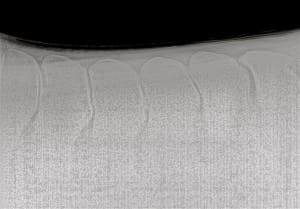

Kissing Spine (Photo: offtrackthoroughbreds.com)

A: Kissing spine, which in technical terms is referred to as the impingement of the dorsal spinous processes, is a diagnosis made through evaluating radiographs of a horse’s back. The condition occurs in the dorsal spinous processes, which is the tips of the spine that you can feel if you press down on the horse’s midline. When they touch or overlap this is considered to be “kissing.”

This radiograph shows no evidence of kissing spine (Photo: offtrackthoroughbreds.com)